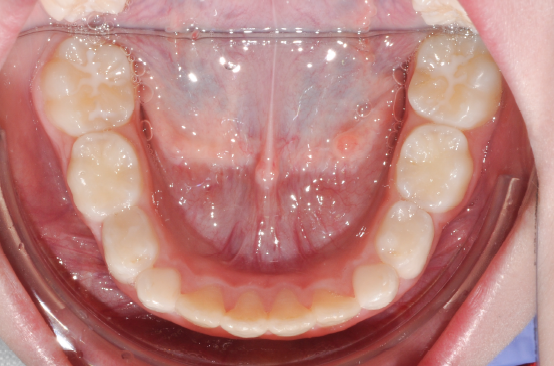

The patient presented with a skeletal Class I relationship and a mesofacial growth pattern, indicating balanced sagittal and vertical skeletal proportions. Dental examination revealed a Class I molar and canine relationship bilaterally. The patient was in the mixed dentition phase. Significant dental crowding was observed in both arches, consistent with a dentoalveolar discrepancy. Midline deviations were present, affecting dental symmetry and occlusal harmony. The maxillary lateral incisors were in crossbite, contributing to anterior transverse discrepancy and functional imbalance.

The orthodontic treatment plan was designed to address dentoalveolar crowding, transverse discrepancies, and midline deviations, while maintaining optimal periodontal health and achieving stable Class I molar and canine relationships. Specific objectives included correction of anterior crossbite, expansion and coordination of the arches, derotation of upper molars, preservation of incisor inclinations, derotation of lower posterior teeth with lingual root torque, leveling of the curve of Spee through incisor intrusion and controlled extrusion of deciduous teeth, and normalization of incisor inclinations. A clear aligner–based approach was selected to allow precise, controlled tooth movement, with particular